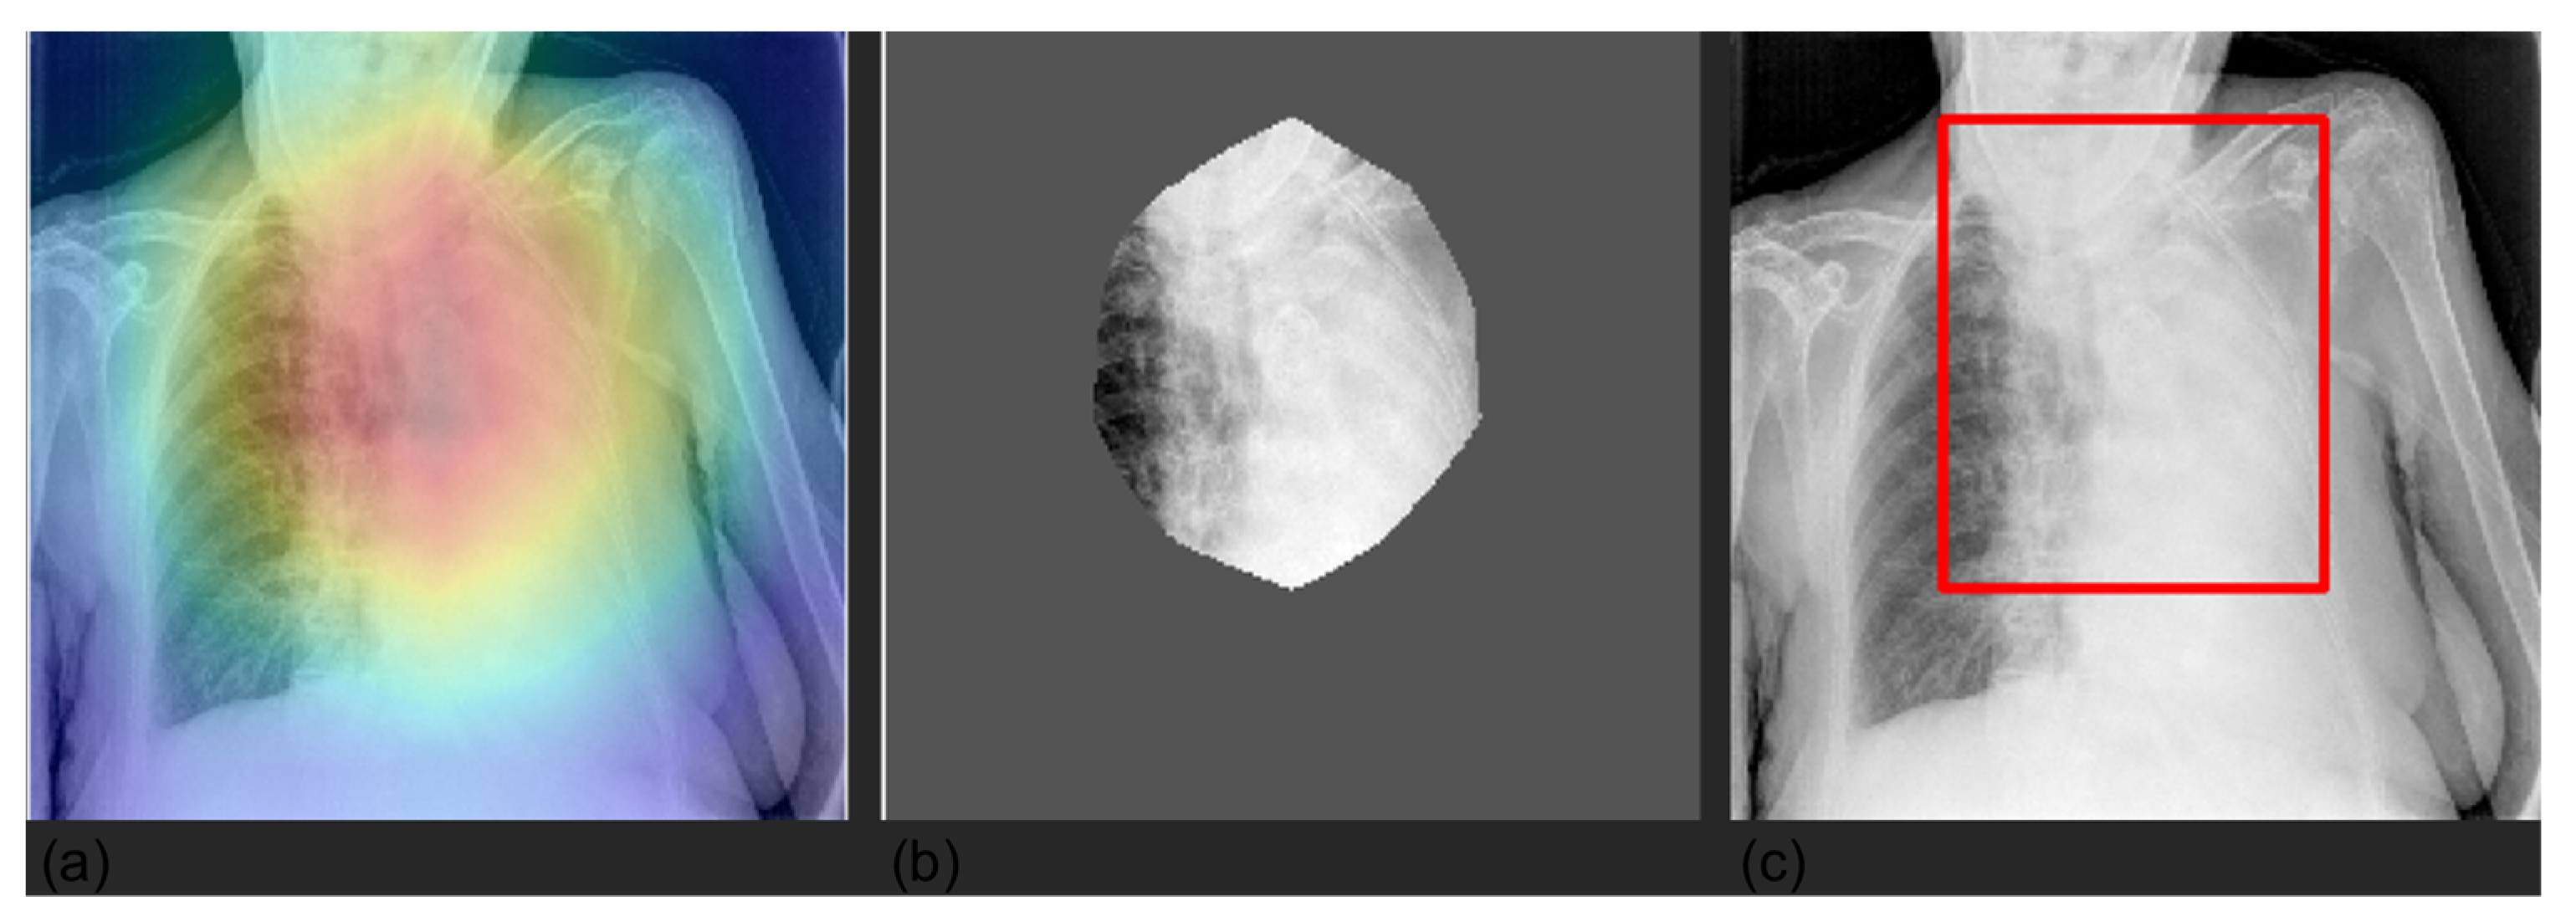

Figure 5.

Visualization of device prediction maps for two selected CXRs. The panels represent the saliency mask obtained with Grad-CAM (panels a,d), the relevant area (mask values higher than the 0.8 quantile) (panels b,e), and the respective bounding box (panels c,f). The saliency mask focuses on device (hardware and/or leads), as shown by the heat map (panel a,d).

Figure 6.

Visualization of pneumothorax prediction maps for a selected CXR. The panels represent the saliency mask obtained with Grad-CAM (panel a), the relevant area (mask values higher than the 0.8 quantile) (panel b), and the respective bounding box (panel c). The saliency mask, as emphasized by the heat map (panel a), focuses on the right lung field, which shows the pneumothorax.

Figure 7.

Visualization of lung prediction maps for a selected CXR. The panels represent the saliency mask obtained with Grad-CAM (panel a), the relevant area (mask values higher than the 0.8 quantile) (panel b), and the respective bounding box (panel c). The saliency mask, as emphasized by the heat map (panel a), focuses on the left lung, which shows lung abnormality.